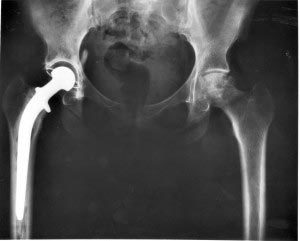

On July 6, 2012, Stryker Orthopaedics issued a recall of its Rejuvenate and ABG II modular hip implants. This hip implant recall followed a recall of the defective product in Canada in the spring of 2012. According to the recall notice posted on the FDA's website, the hip implants have been recalled because of a fretting and corrosion at the modular neck junction. This deterioration leads to the deposit of metal ions into the soft tissue surrounding the hip joint, which results in metallosis, necrosis, and osteolysis, any of which may result in the need for a revision surgery, where the hip implant is removed and replaced with another implant.

recalled two if it's metal-on-metal hip implants and several other metal-on-metal hip implants have been discontinued. Recently, the FDA convened a panel of experts to evaluate metal-on-metal hip implants. Although the panel did not recommend an outright recall of all metal-on-metal hip implants, it did find little reason to use the implants and cautioned doctors against their use. Although the Rejuvenate and ABG II models do not have the same design defect as many of the metal-on-metal hip implants, which are susceptible to excessive wear on the articulated surfaces of the femoral head and acetabular cup, the developing data indicates that there is a design defect in modular neck junction of these devices.

Stryker began selling the Rejuvenate and ABG II models in the United States in 2009. Post-market surveillance of the device disclosed excessive adverse event reports suggestive of a trend toward an unusually high failure rate. Patients have complained of pain, swelling, and discomfort in the hip area. If you are experiencing any of these symptoms, you should contact your orthopedic surgeon and have your hip implant evaluated. You should also contact a lawyer knowledgeable about the Stryker Rejuvenate hip implant recall and the developing litigation.